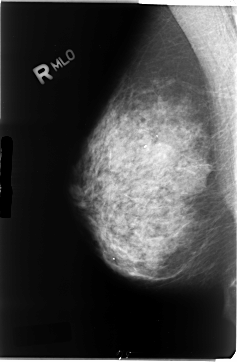

B_3044_1.RIGHT_MLO

RIGHT_MLO LINES 4696 PIXELS_PER_LINE 3080 BITS_PER_PIXEL 12 RESOLUTION 50 NON_OVERLAY